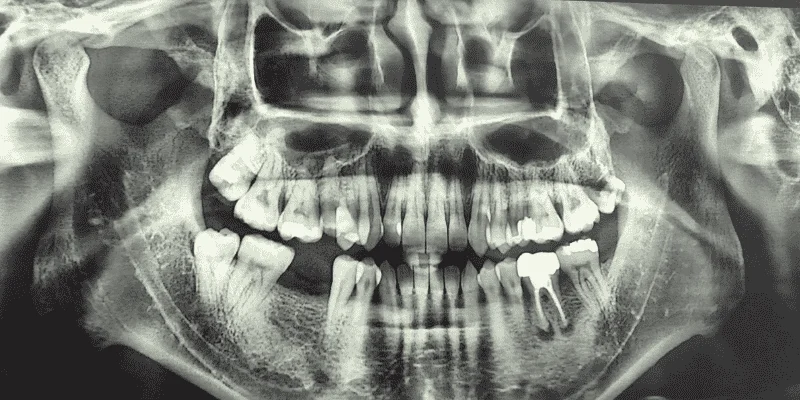

The Chain Reaction After Losing a Tooth

Your mouth works as a complete system where each tooth supports the others. When you lose a tooth, the empty space triggers a series of problems that get worse over time.

The teeth next to the gap will start to shift and tilt toward the open space. Your opposing teeth may also drift up or down into the empty spot.

This movement happens because teeth need neighbors to stay in place. Delaying tooth replacement leads to jawbone deterioration in the area where your tooth used to be.

Your jawbone needs pressure from tooth roots to stay strong and healthy. Without that pressure, the bone starts to break down within weeks of tooth loss.

When you lose a tooth, the surrounding teeth start to move. The teeth next to the gap drift sideways to fill the empty space.

The tooth above or below the missing one can also shift down or up. This movement throws off your bite alignment.

Your teeth work together as a system, and losing a tooth starts a chain reaction that affects nearby teeth. The jawbone underneath the empty space also begins to shrink because it no longer gets stimulation from the tooth root.

Your other teeth may tilt or rotate into the gap. This shifting creates gaps between teeth that were not there before.

These changes make it harder to clean your teeth properly and can lead to decay and gum disease.